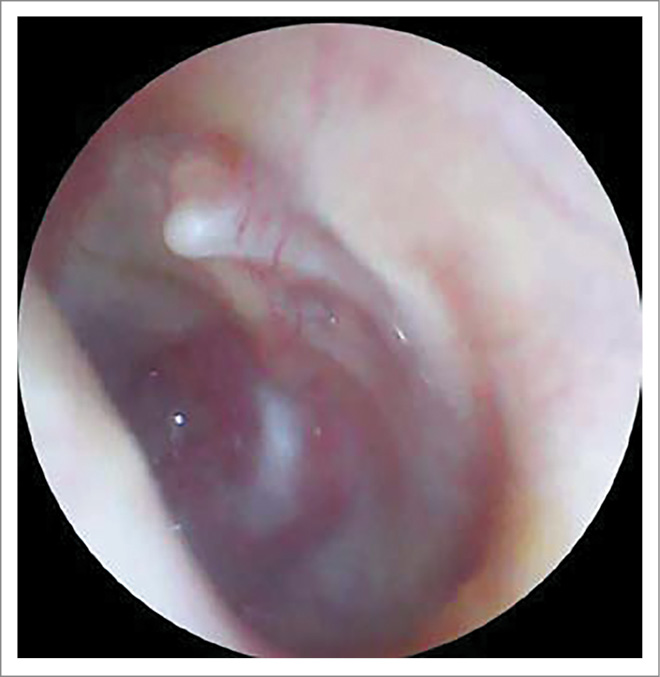

AS – околоушная, заушная область не изменена, при пальпации безболезненна. При отоскопии: наружный слуховой проход широкий, свободный, БП утолщена, местами гиперемирована, в передних отделах визуализируется центральная перфорация диаметром 2 мм, при выполнении пробы Вальсальвы из перфорации поступает скудное гнойное отделяемое (рис. 2).

Рис. 2. Отоскопическая картина слева при поступлении: БП утолщена, местами гиперемирована, в передних отделах визуализируется центральная перфорация диаметром 2 мм.